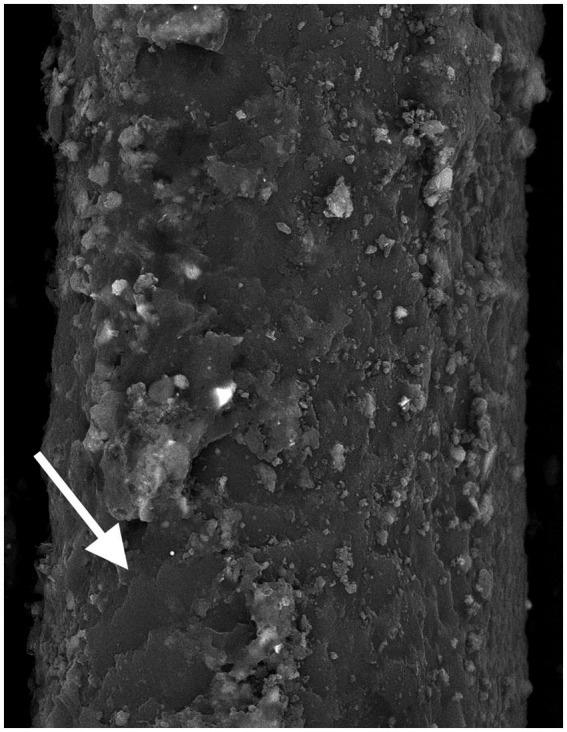

Computed tomography estimated the age of death to be 48.1 years ±14.6 based on the pubic symphyseal surface. CT detected mild-to-moderate teeth attrition, and joints degeneration. The desiccated brain and viscera remained . FTIR revealed the wig is formed of midrib date palm that shows in CT as spiral low density fibers. The wig fibers are partially coated with a thick substance that is inspected as black consolidation and identified as crystalline by XRD, comparable to material found in an ancient wig-making workshop. FTIR showed that the skin, hair, and wig samples were treated with imported juniper resin had anti-bacterial and insecticidal properties. The skin and wig samples contained frankincense, and the hair sample contained henna.

基于耻骨联合面,CT估计死亡年龄为48.1岁±14.6岁。CT检测到轻度至中度的牙齿磨损和关节退变。干燥的大脑和内脏得以保留。FTIR显示假发由枣椰树的中脉形成,在CT中表现为螺旋状低密度纤维。假发纤维部分被一种厚实物质覆盖,在CT中被检测为黑色固结物,经XRD鉴定为晶体,与在一个古代假发制作工坊中发现的材料类似。FTIR表明皮肤、头发和假发样本用具有抗菌和杀虫特性的进口杜松树脂进行了处理。皮肤和假发样本含有乳香,头发样本含有指甲花。